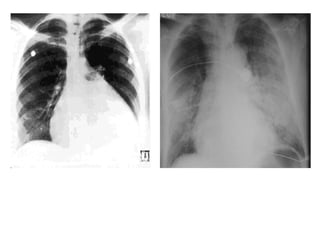

Cardiomyopathy   Pulmonary Edema

Clinical Data • CXR – Kerley’s lines : A and B – Pulmonary Edema – Pleural Effusions (bilateral) • EKG – Left atrial enlargement – Arrhythmias – Hypertrophy (left or right)